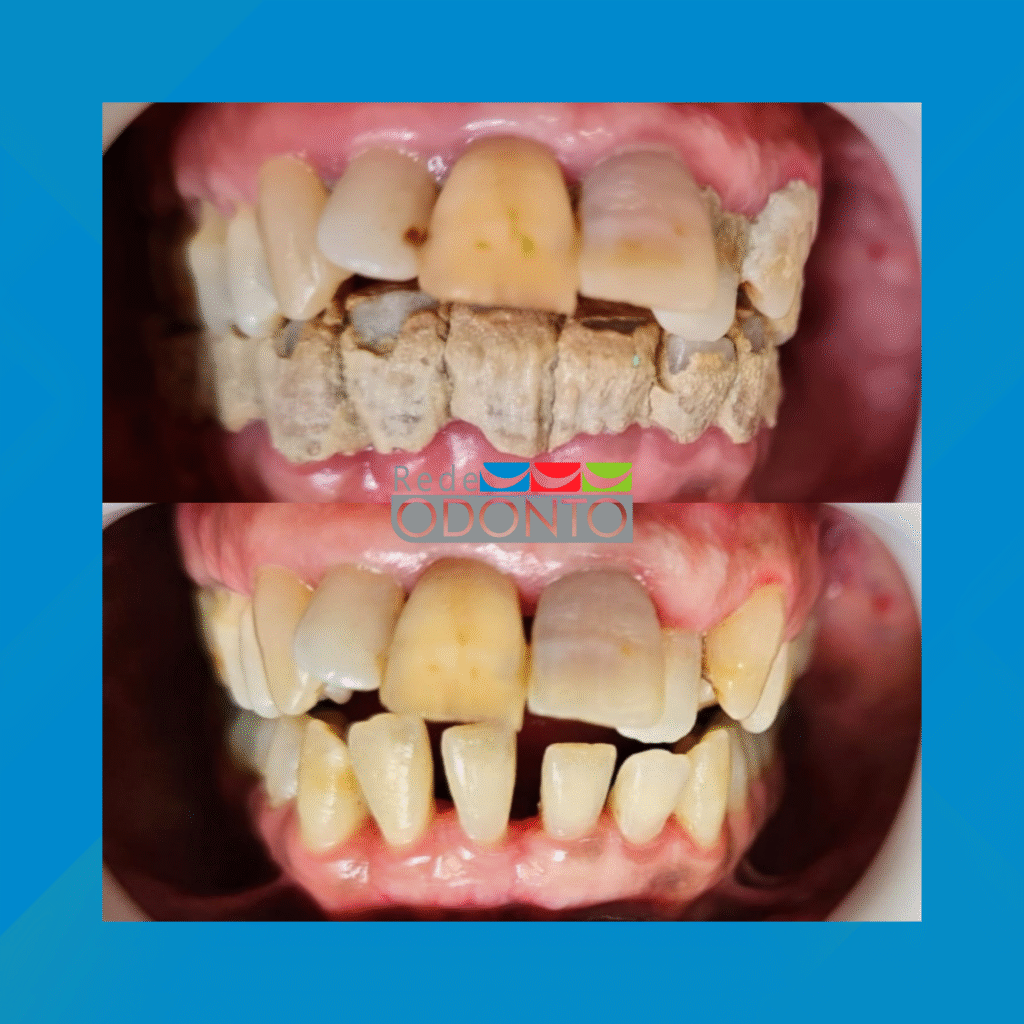

Manter o sorriso bonito e saudável começa com a Limpeza Dental Profissional. Este procedimento é crucial para remover a placa bacteriana e o tártaro (cálculo) que a escovação diária não alcança.

2. Raspagem (Tratamento Periodontal): Indicada quando o tártaro se acumulou abaixo da linha da gengiva (subgengival). É um tratamento mais profundo, essencial para eliminar o tártaro que causa inflamação e doenças gengivais (gengivite e periodontite), evitando a perda óssea e dentária.